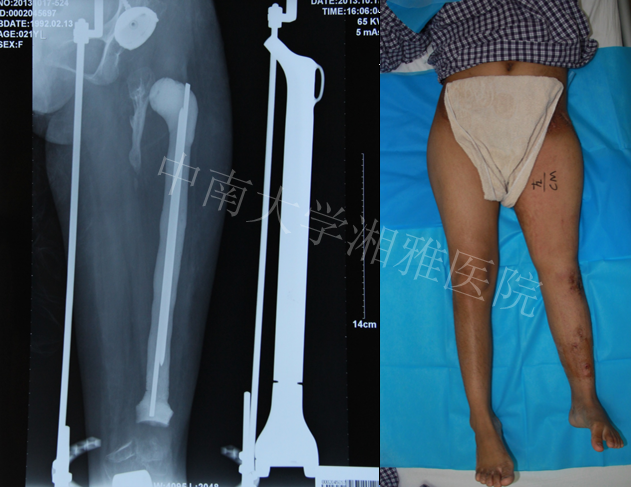

2013年5月髋臼置换

2013年6月安装胫骨侧假体,自制股骨骨水泥占位器占位,继续延长

2013年10月复查双下肢长度恢复